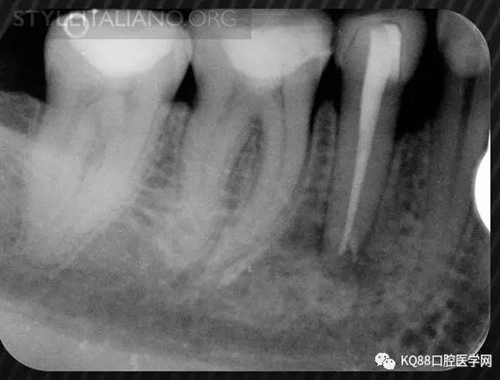

Case 1: In this patient, persistent pain was present after endodontic treatment of a vital tooth. The periapical x-ray showed an inadequate shaping of the distal root canal, regarding both the working length and the apical taper.